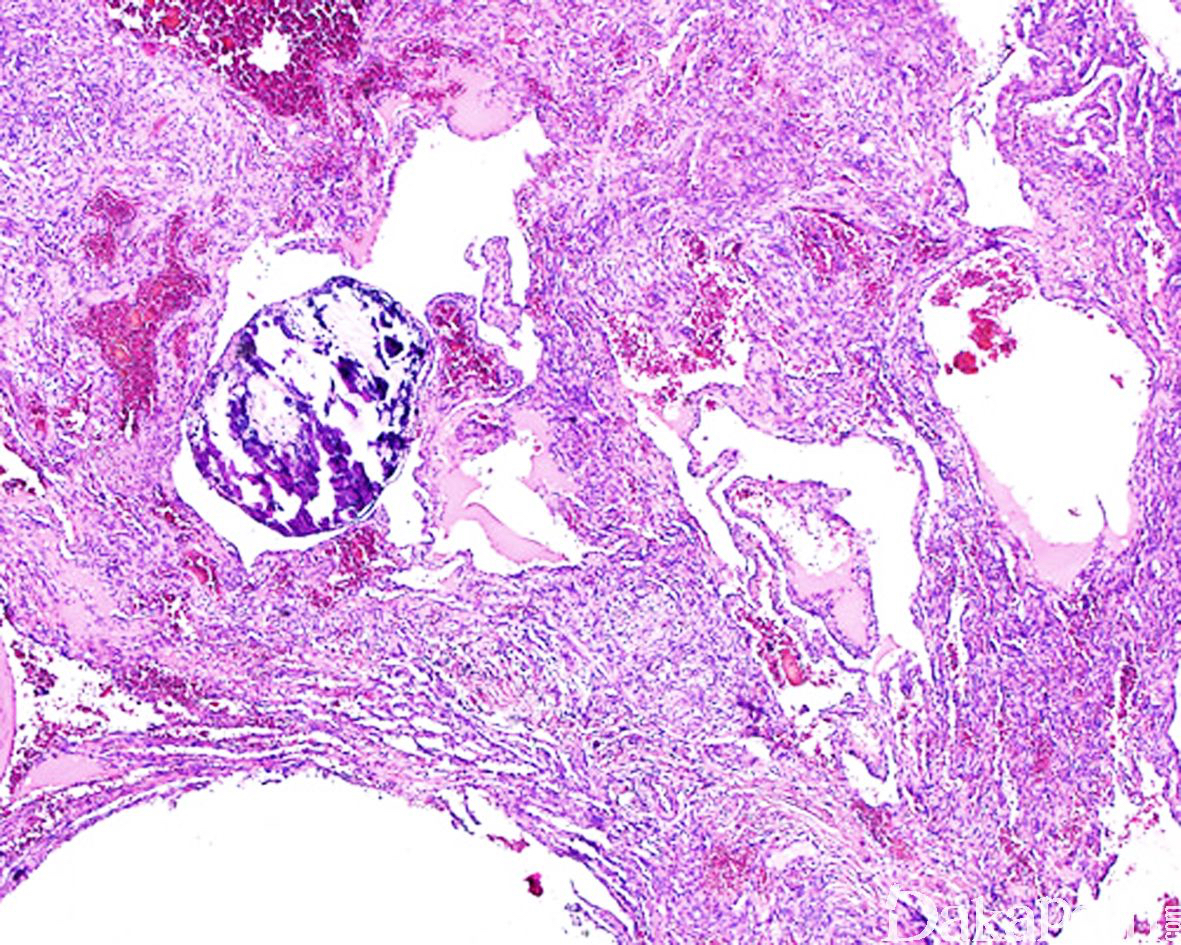

病变直径较小,通常< 2cm, 位于真皮或皮下,偶尔可位于深部软组织,组织学呈多结节状生长,主要由海绵状血管瘤样区域和实性梭形细胞区域两种成分组成,梭形细胞成分达 50%以上;

海绵状血管瘤样区域内的血管多为扩张的薄壁血管,大小不一,内衬扁平内皮细胞,常充满血液,可伴血栓形成;

实性区域梭形细胞多和海绵状血管瘤样区域相互交融,梭形细胞呈短束状排列,其中血管或为扩张的薄壁血管,或呈不规则裂隙样,间质内常可见外渗的红细胞,类似卡波西肉瘤;

除梭形细胞外,实性区域内还可见小簇分布的圆形空泡状细胞,形态与上皮样血管内皮瘤中的空泡状细胞相似,似形成原始性脉管腔,当空泡状细胞数量较多时可类似于脂肪母细胞;瘤细胞核温和,少数可见退变的核非典型性,核分裂象罕见(< 1/50HPF);

约 50%的梭形细胞血管瘤可见肿瘤于血管内生长,10-20%的梭形细胞血管瘤可完全位于血管内。取决于血管瘤样成分和梭形细胞成分的比例多少,梭形细胞血管瘤在低倍镜下可能类似于海绵状血管瘤或 Kaposi 血管肉瘤;